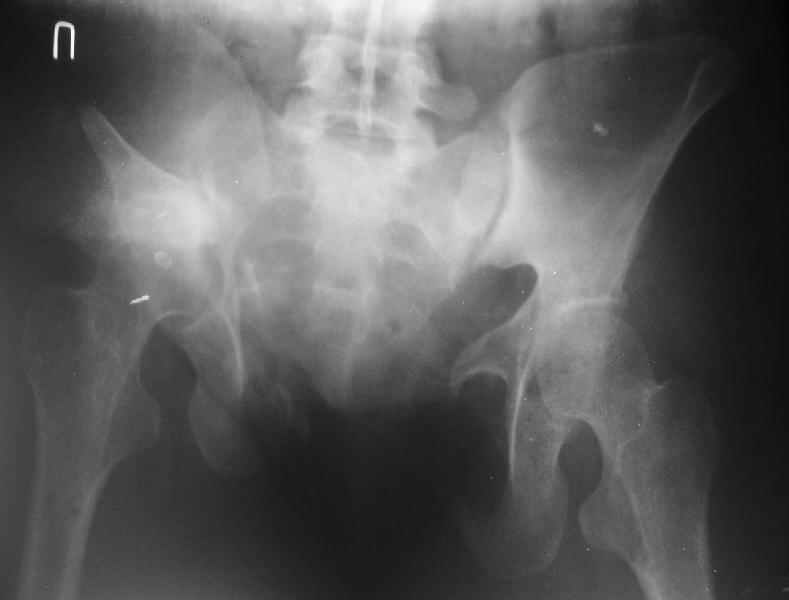

Снимки до лечения: